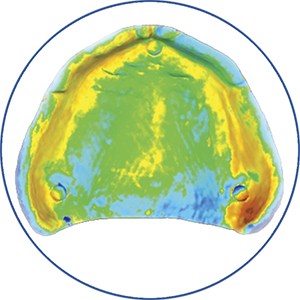

Met de AvaDent immediaat prothese kan de bestaande dentitie eenvoudig worden overgenomen. Dankzij de digitale back-up kunnen kleur, stand en vorm worden overgenomen bij het vervaardigen van de uiteindelijke prothese. De immediaat prothese is volledig monolitisch, tot wel 8 keer sterker en zorgt voor minder last van drukplekken.